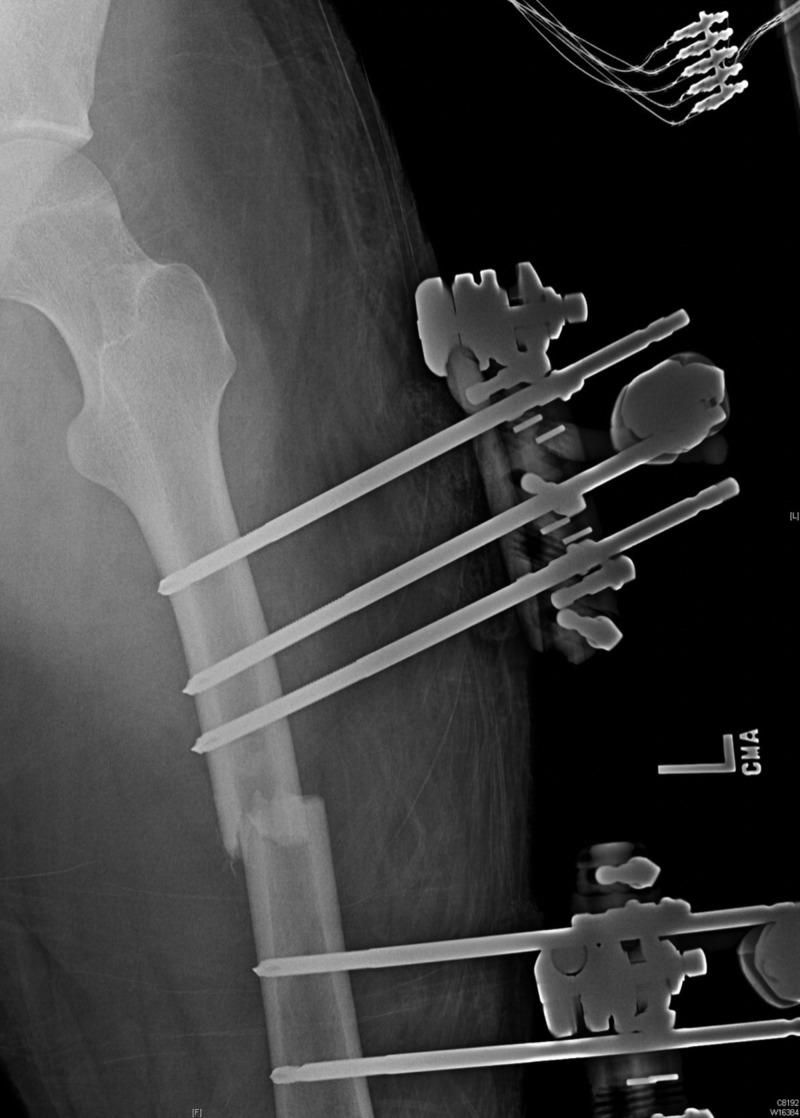

Fat embolism syndrome (FES) is a rare event following a traumatic injury, and its pathophysiologic mechanism continues to be elusive. Fat embolism syndrome generally occurs when a bone marrow fat enters the bloodstream resulting in a cascade of inflammatory response, hyper-coagulation, and an array of symptoms that generally begin within 24-48 hours. FES early symptoms include petechial rash, shortness of breath, altered mental status, seizures, fever, and may result in decreased urine output. The common etiologies of a fat embolism include long bone fractures, mainly femoral and pelvic fractures. There are multiple management methods described in the literature to help prevent FES and other long bone fracture complications from occurring. Although not universally adopted, the damage control orthopedics (DCO) has been the major management option for patients with a long bone fracture. DCO is entertained by provisional immobilization of patients with long bone fractures and those who are considered severely traumatized patients (STP). Thus, immobilization can help minimize the traumatic effect and the subsequent second hit by performing non-life saving surgical procedures. In this case, a patient with a transverse femur fracture suffered disconcerting symptoms of fat embolism prior to definitive femur repair. Hence, damage control orthopedics was entertained with a postponement of his femur repair to facilitate stabilization. The use of damage control orthopedics was successful in this patient with no long term complications.